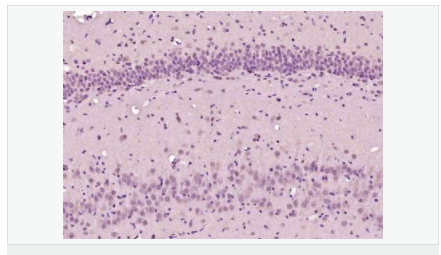

產(chǎn)品介紹Involved in the formation and segmentation of paraxial mesoderm. Has the regulatory capacity to specify ventrolateral (including future paraxial), but not dorsal (future axial), mesoderm phenotypes. Seems to be an upstream regulator of at least some elements of the Notch and Delta signaling pathway.

Involved in specifying the paraxial, but not dorsal, mesoderm. May regulate the expression of T-box transcription factors required for mesoderm formation and differentiation (By similarity).

Subcellular Location:

Contains 1 basic helix-loop-helix (bHLH) domain.